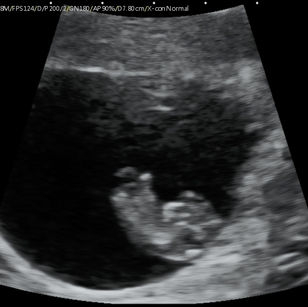

9 Weeks Pregnant

Size: ~0.9 inch (2.3 cm), the size of a Grape!

Development Highlights:

Limbs grow longer; elbows and knees visible.

Tooth buds appear under gums.

Eyes more developed, but eyelids remain fused.

Brain continues rapid development; nervous system forming connections.